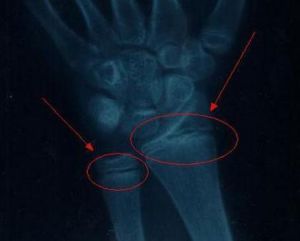

骨骺線先天性因素:(1)營養代謝障礙(維生素A、D過剩症);(2)骨折(外傷性、病理性);(3)放射性損傷;(4)骺板軟骨區感染(化膿性、結核性);(5)骺板軟骨燒傷、凍傷、創傷等;(6)大骨節病;(7)氟中毒;(8)小兒氟骨症。導致骨骺早閉的病因發生越早,畸形會越重,愈後也就越差。對國家、社會、家庭均帶來較重的經濟負擔,給患兒也會帶來一定的思想和精神壓力,。學者認為有些引起骺早閉的病因是完全可以避免的,有些病因雖能導致患兒致殘,但如果積極防治可降低致殘率的發生和減輕畸形。為此應注意以下幾個方面:

3、教育兒童加強自我保護避免各類創傷。骨關節跌傷後,應立即到有經驗的骨傷科(矯形外科)去整復治療,以免延誤診治,造成嚴重骨骺早閉畸形。

4、對一些導致骨骺早閉的地方病,意外事故、車禍、燒傷、凍傷等均應進行有針對性的積極防治,儘可能將畸形減少到最低程度。

目前各種骨骺早閉畸形肌體可以進行手術矯正及整形,使殘疾關節與畸形肌體功能得到部分恢復和改善。